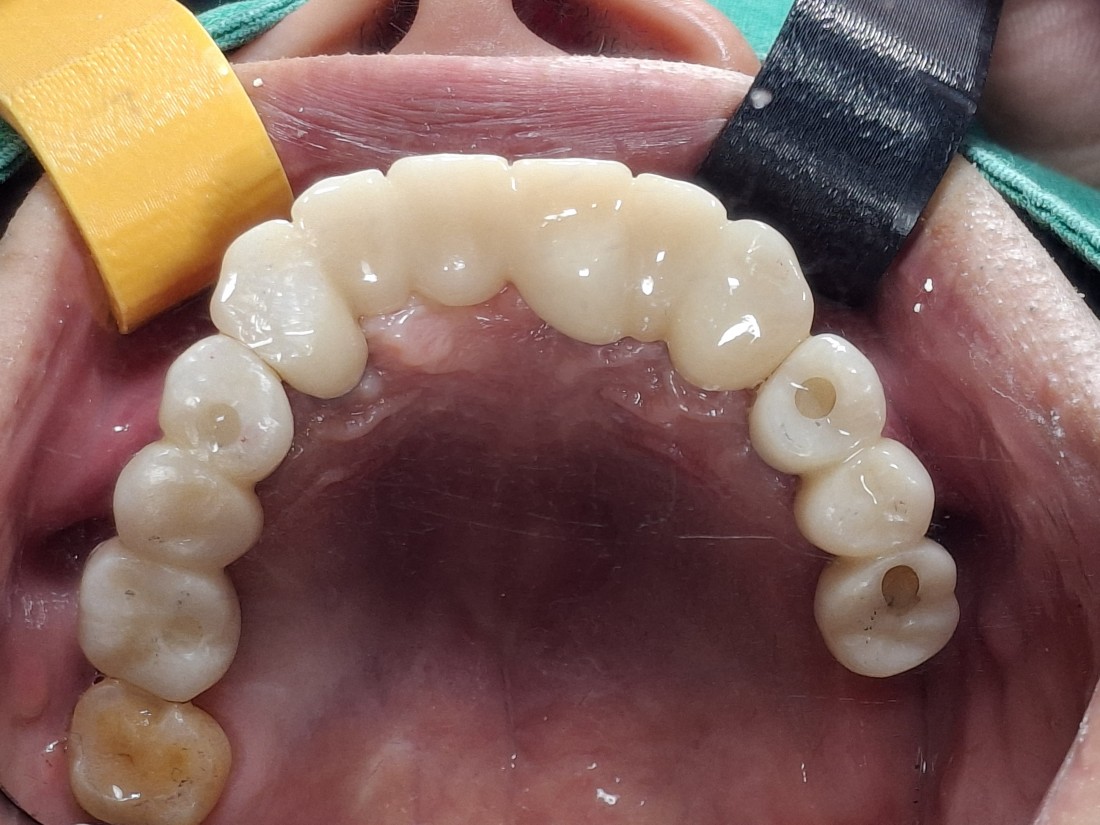

전남광주 임플란트치과에서는

잇몸절개를 하지 않고 무절개로 하거나,

최소한으로만 절개하는

디지털 가이드 임플란트 수술을 하기 때문에

임플란트 수술 후에

붓기, 출혈, 통증이 매우 적습니다.